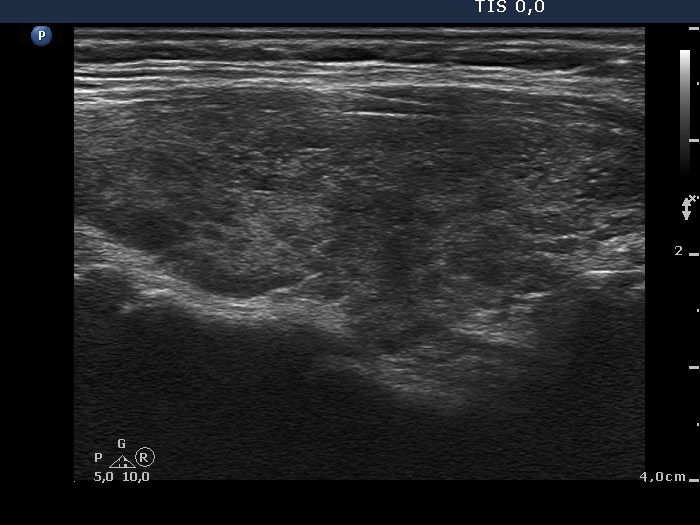

Consecutively operated patients with autoimmune thyroid disease - case 55 (1184) (ultrasonographic picture 5)

Left lobe, longitudinal view.